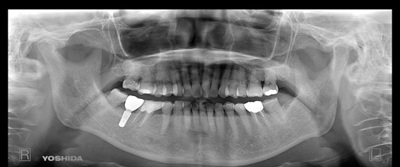

術前パノラマ